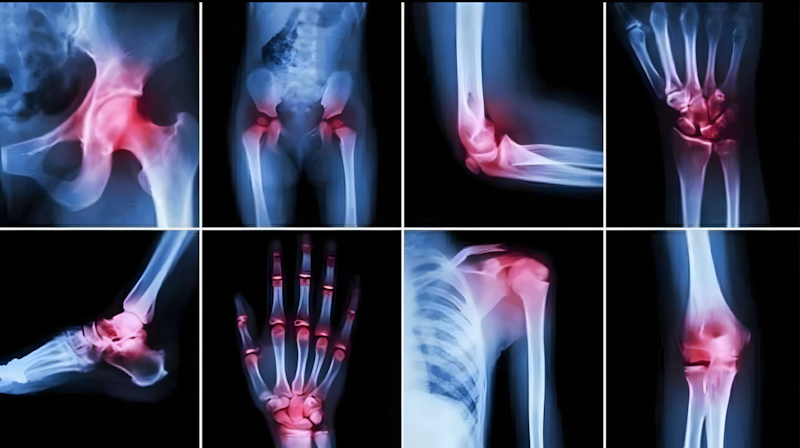

Manieren om van gewrichtspijn af te komen

Gewrichtspijn is een van de meest voorkomende gezondheidsproblemen die mensen van alle leeftijden treffen, vooral bij het ouder worden, lange werkdagen of langdurig stilzitten. Gewrichten zijn de punten waar botten samenkomen en het lichaam flexibiliteit en beweging geven. Elke disfunctie of slijtage in deze gewrichten leidt tot aanhoudende pijn en stijfheid, en soms tot problemen met lopen of het uitvoeren van dagelijkse taken.